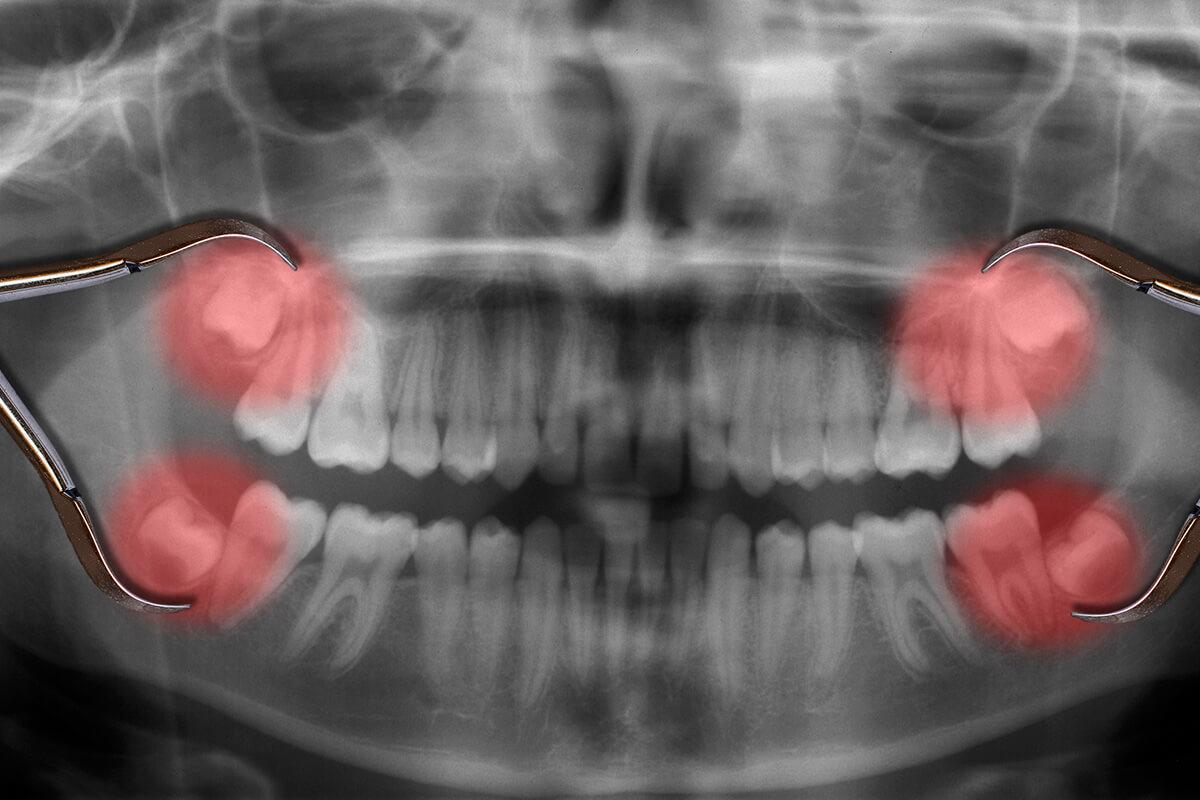

Consultation & X-rays

Assess tooth position and plan treatment.Anaesthesia Options